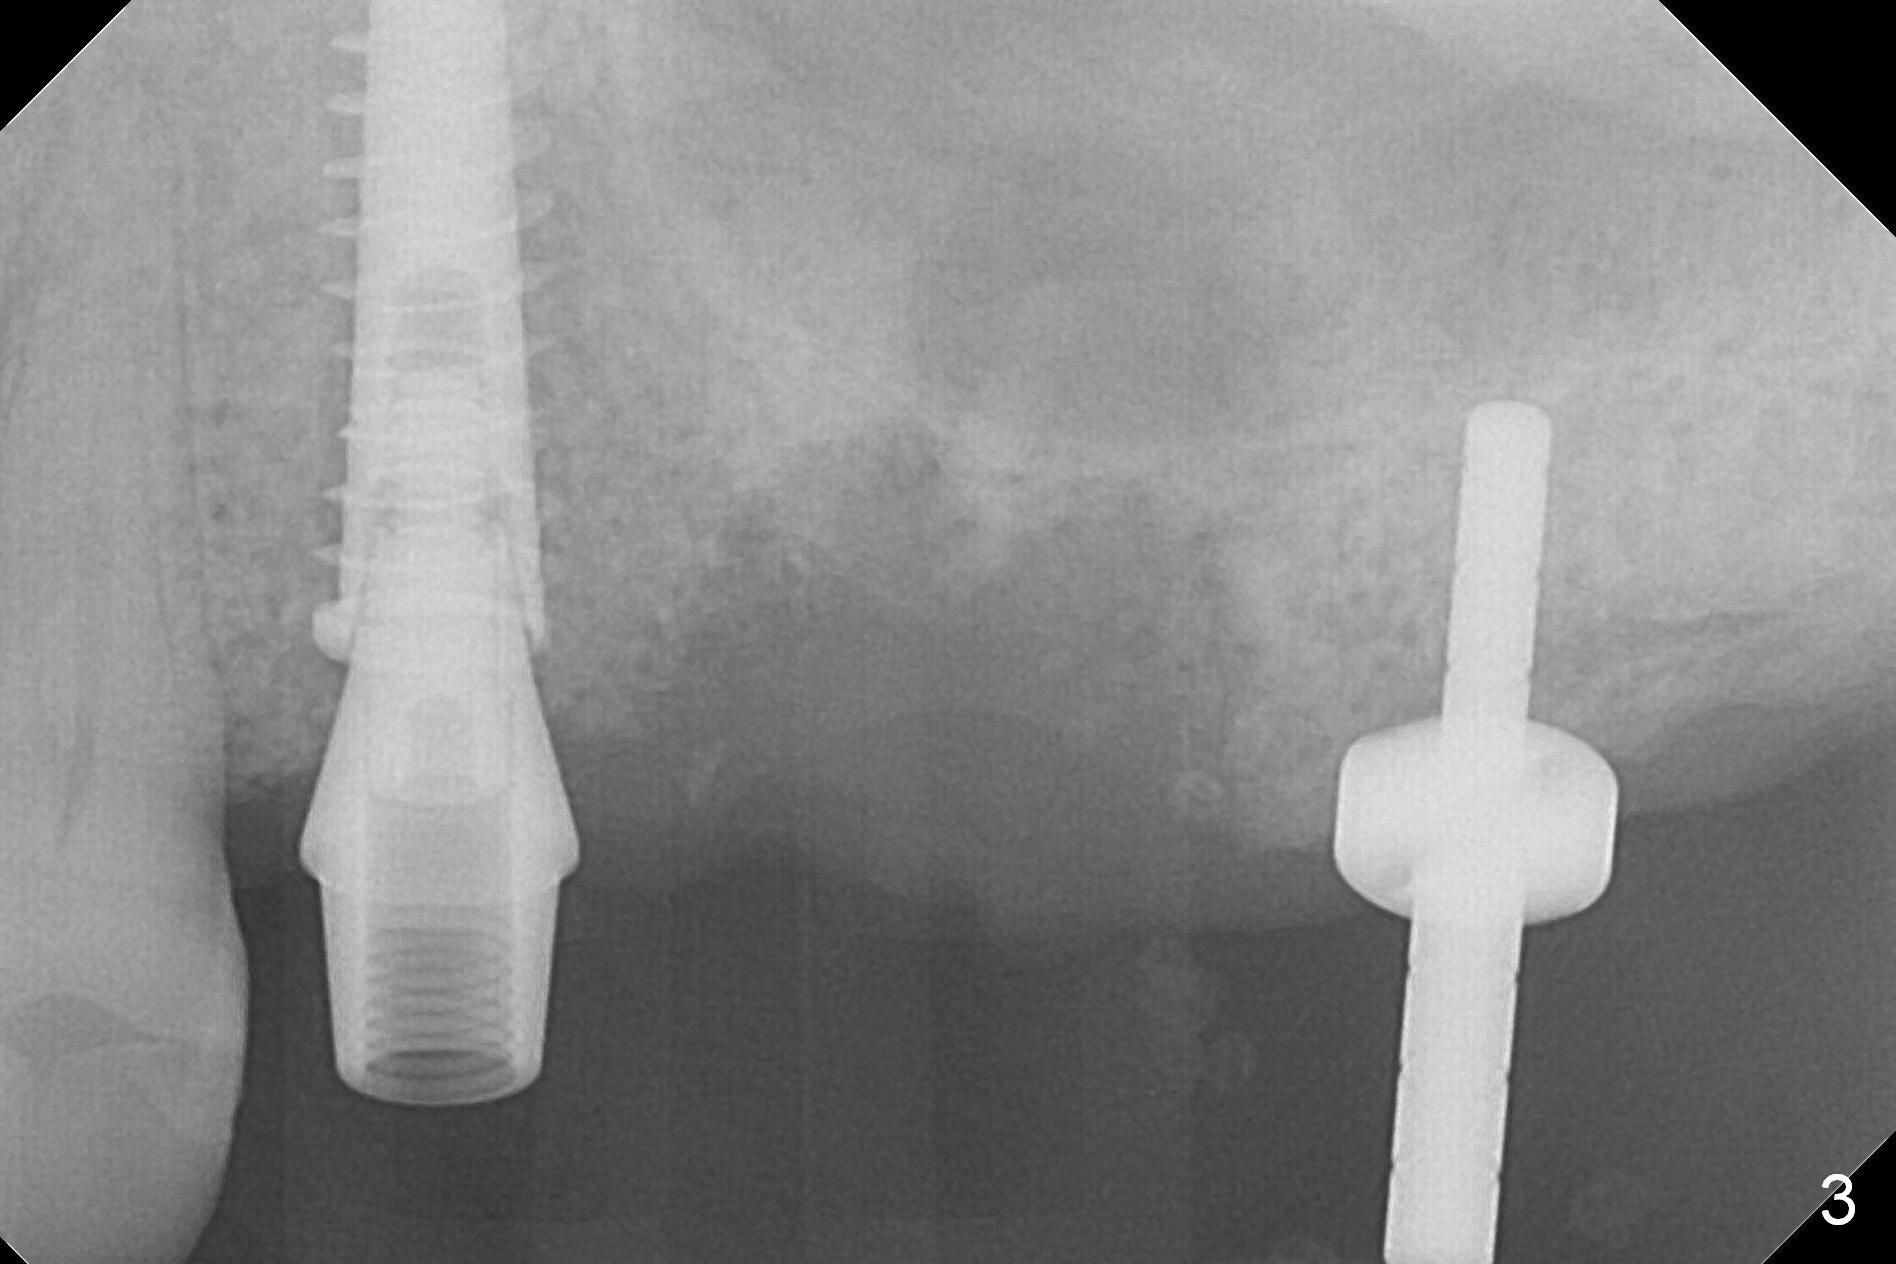

Following placement of a 4.5x13 mm IBS implant (>50 Ncm) and 5x4(3) mm pair abutment, the cantilever bridge is removed. Bone loss at #14 is so severe that an immediate implant seems to be inappropriate. Finance is another factor. Osteotomy is initiated at #15, followed by insertion of a parallel pin (Fig.3).